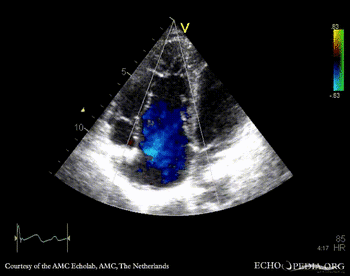

A4CH: Color Doppler, severe tricuspid regurgitation Continuous-wave signal of severe tricuspid regurgitation, pulmonary hypertension